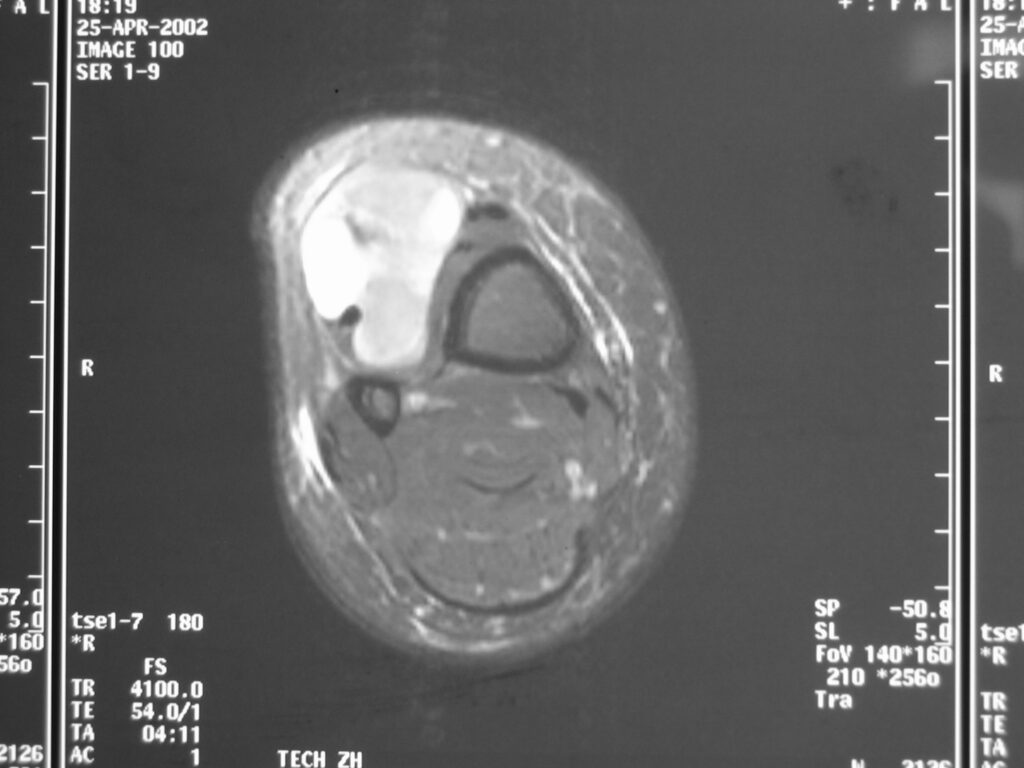

MRI

Shows multiloculated, heterogeneous mass.

“Triple Signal Intensity sign”; hypointense, isointense and hyperintense with fat on T2 – weighted MRI imaging. This sign is present in 30 to 50% of the cases. (Fig.3)

Under contrast enhancement Synovial Sarcoma appears heterogeneous and demonstrate areas of nodular enhancement.

In approximately 30% of cases a multiple vascular cannel may be identified

Synovial sarcomas may have a cystic appearance and are often mistaken for ganglion cysts especially those adjacent to tendons and in the foot and ankle.